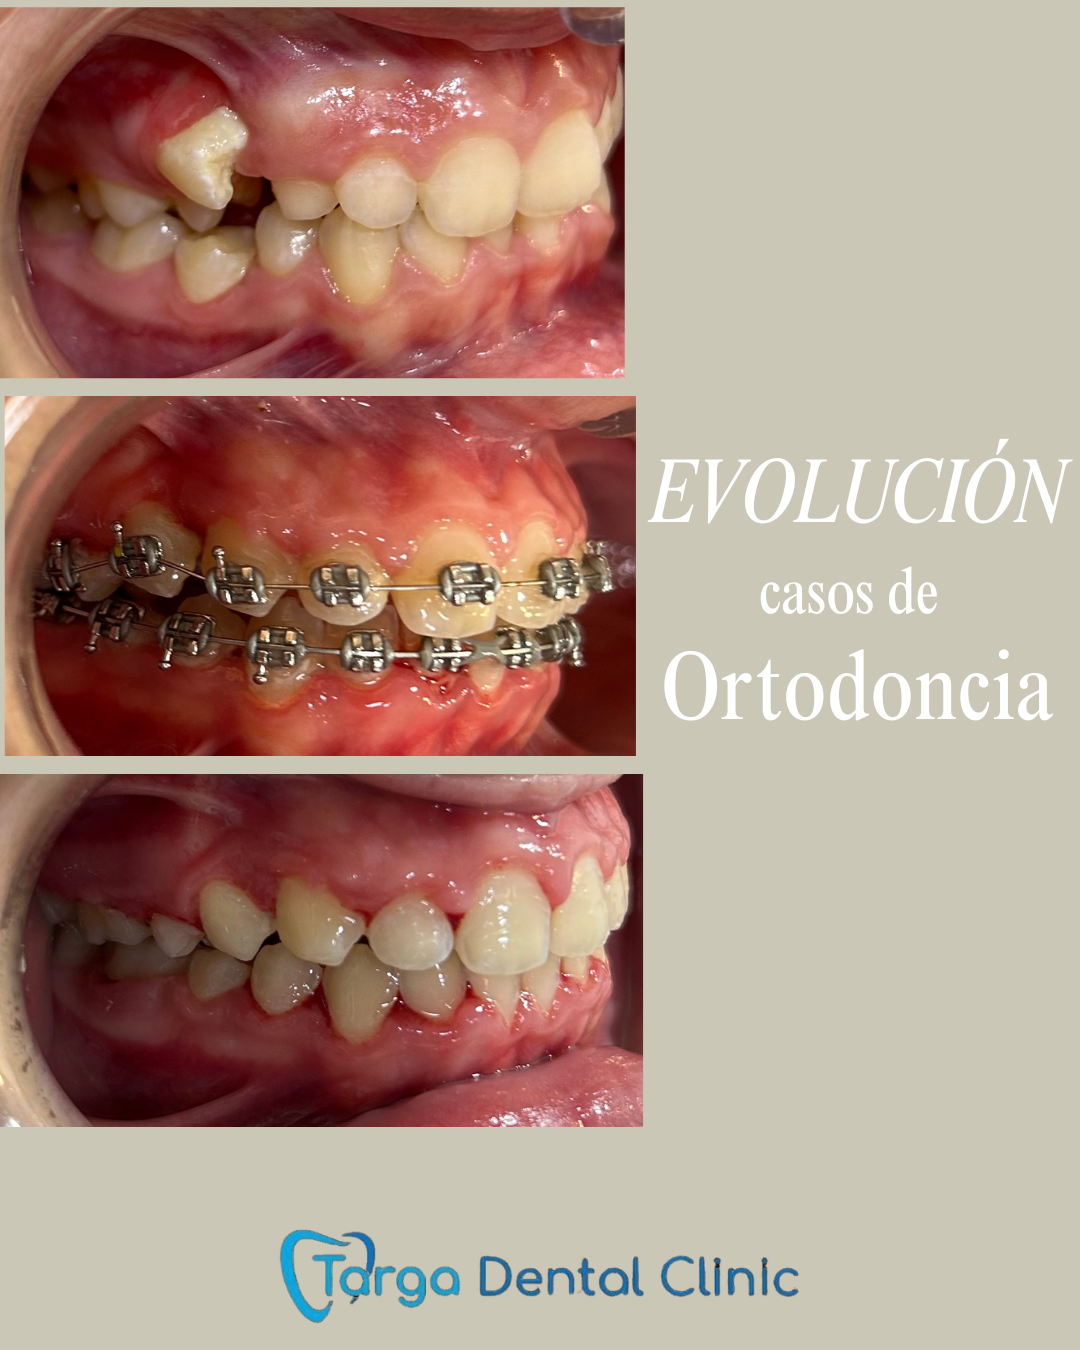

Ortodoncia y Odontopediatría

Ofrecemos tanto ortodoncia invisible con alineadores como ortodoncia fija con brackets.

Evaluamos cada caso y te recomendamos el más adecuado para ti. También ortodoncia para los más pequeños y los pacientes en crecimiento.

Tratamientos realizados en nuestra clínica